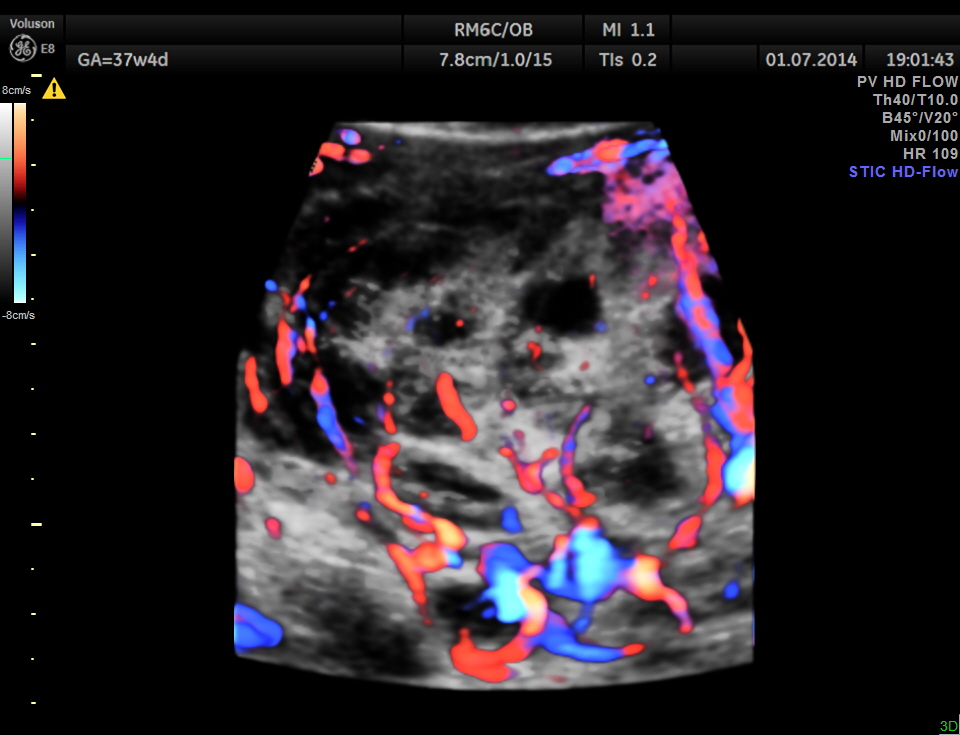

The placenta was on the anterior wall and the scan showed a distinct mass lesion in the antero right lateral portion. The placenta had multiple small cystic appearance in the right lateral aspect . Colour doppler showed no increased vascularity.

She came again after 2 months .The placenta appeared nearly the same , but showed more vascularity.